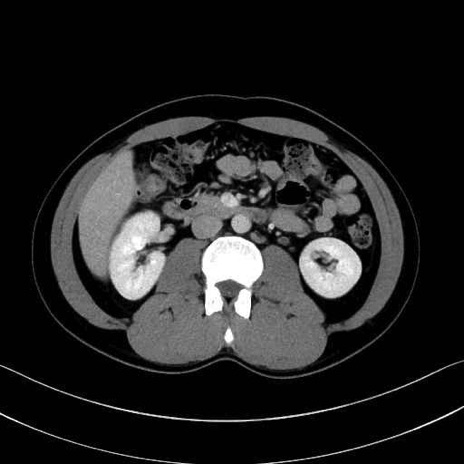

【症例】20歳代 男性 スクリーニング

脾動脈の画像解剖

■起始:典型的には腹腔動脈幹(celiac trunk)から左胃動脈・総肝動脈とともに三分岐し、脾動脈は左後上方へ向かう。

■走行:膵上縁または膵実質背側を蛇行しながら左方へ進み、膵尾部近傍で脾門へ至る。蛇行の程度は個体差が大きい。

■終枝:脾門部で複数の終末枝に分かれ、上極・下極枝や脾門枝群を形成する。胃短動脈群や左胃大網動脈はしばしば脾動脈から分岐する。